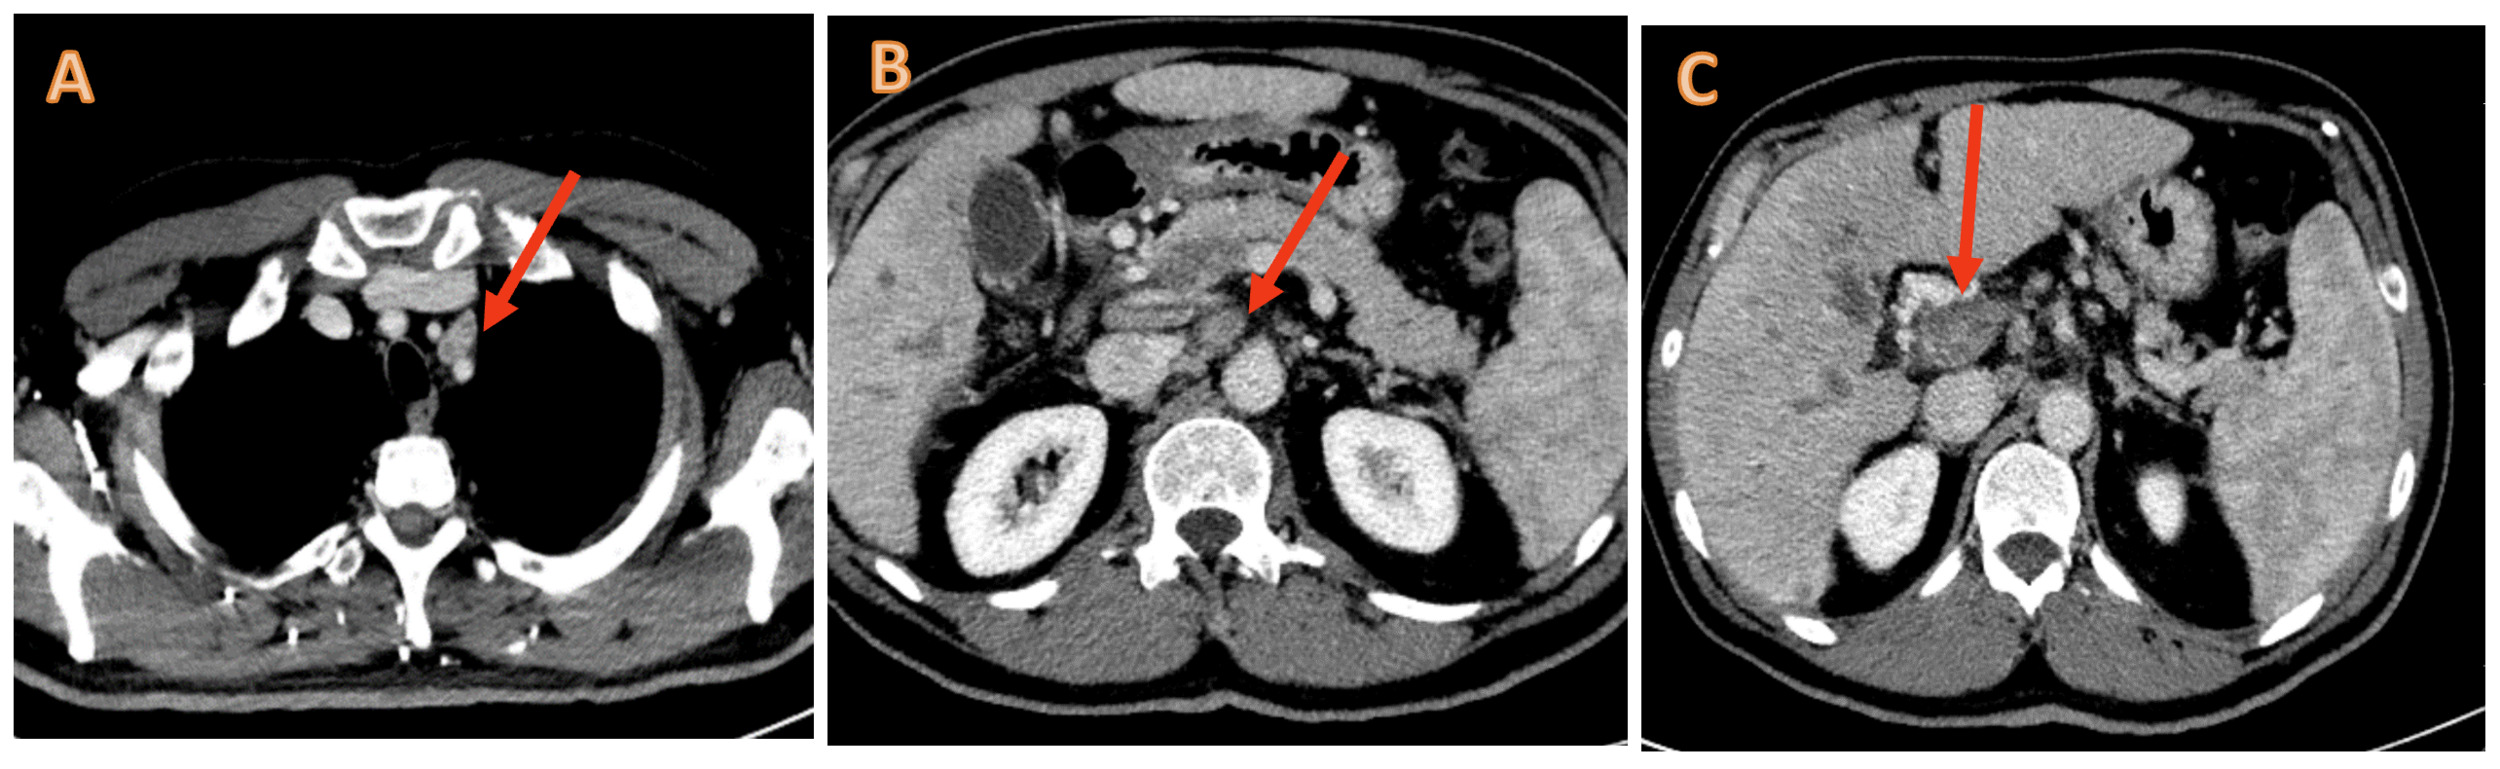

We performed a new thorax-abdomen CT scan that showed excellent response to treatment, with an important reduction of the known liver lesions (Figures 7−8). There was also a significant reduction in the value of alpha-fetoprotein (from 131 μg/L at the beginning of the treatment to 7.2 µg/L after 3 cycles of therapy).